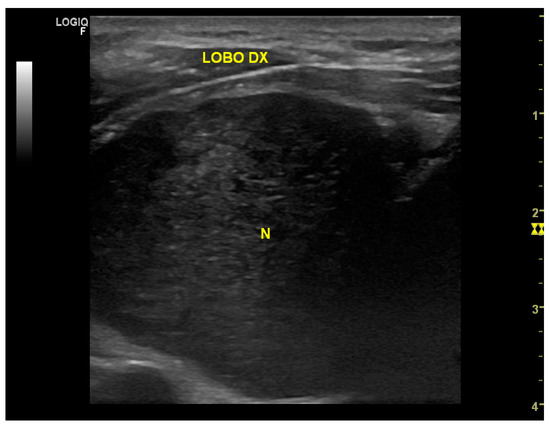

| De Paoli et al., 2005 [23] | 63/F | Foreign body sensation with swallowing | 27 mm—Lower pole of right thyroid lobe | US: Markedly hypoechogenic nodule with rich vascularity | Fragments of adipose tissue, rare thymocytes in aggregates resembling follicular masses, insufficient for diagnosis | Total thyroidectomy | Schwannoma in the perithyroid tissue, with compact areas of spindle cells or Verocay bodies (Antoni A) and loosely arranged foci (Antoni B) | |